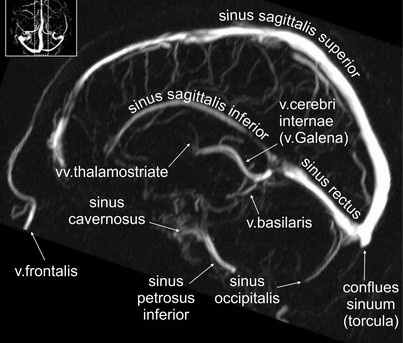

Как известно, синусы ТМО располагаются между двумя ее листками и дренируются во внутренние яремные вены. Основные синусы представлены на схеме выше.